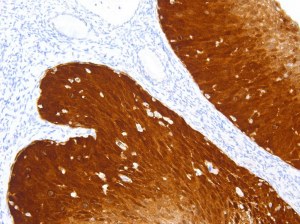

De LymphoSign-kit speelt een cruciale rol bij het stellen van een juiste diagnose en het opstellen van een behandelplan voor non-Hodgkin-lymfoom. Deze geavanceerde methode maakt gebruik van RNA-expressieniveaus van meer dan 130 relevante genmarkers en biedt waardevolle inzichten in het ziekteverloop. Dankzij het eenvoudige, snelle protocol en de geschiktheid voor uitdagende monsters is het een krachtig hulpmiddel bij onderzoek naar non-Hodgkin-lymfoom en patiëntenzorg .